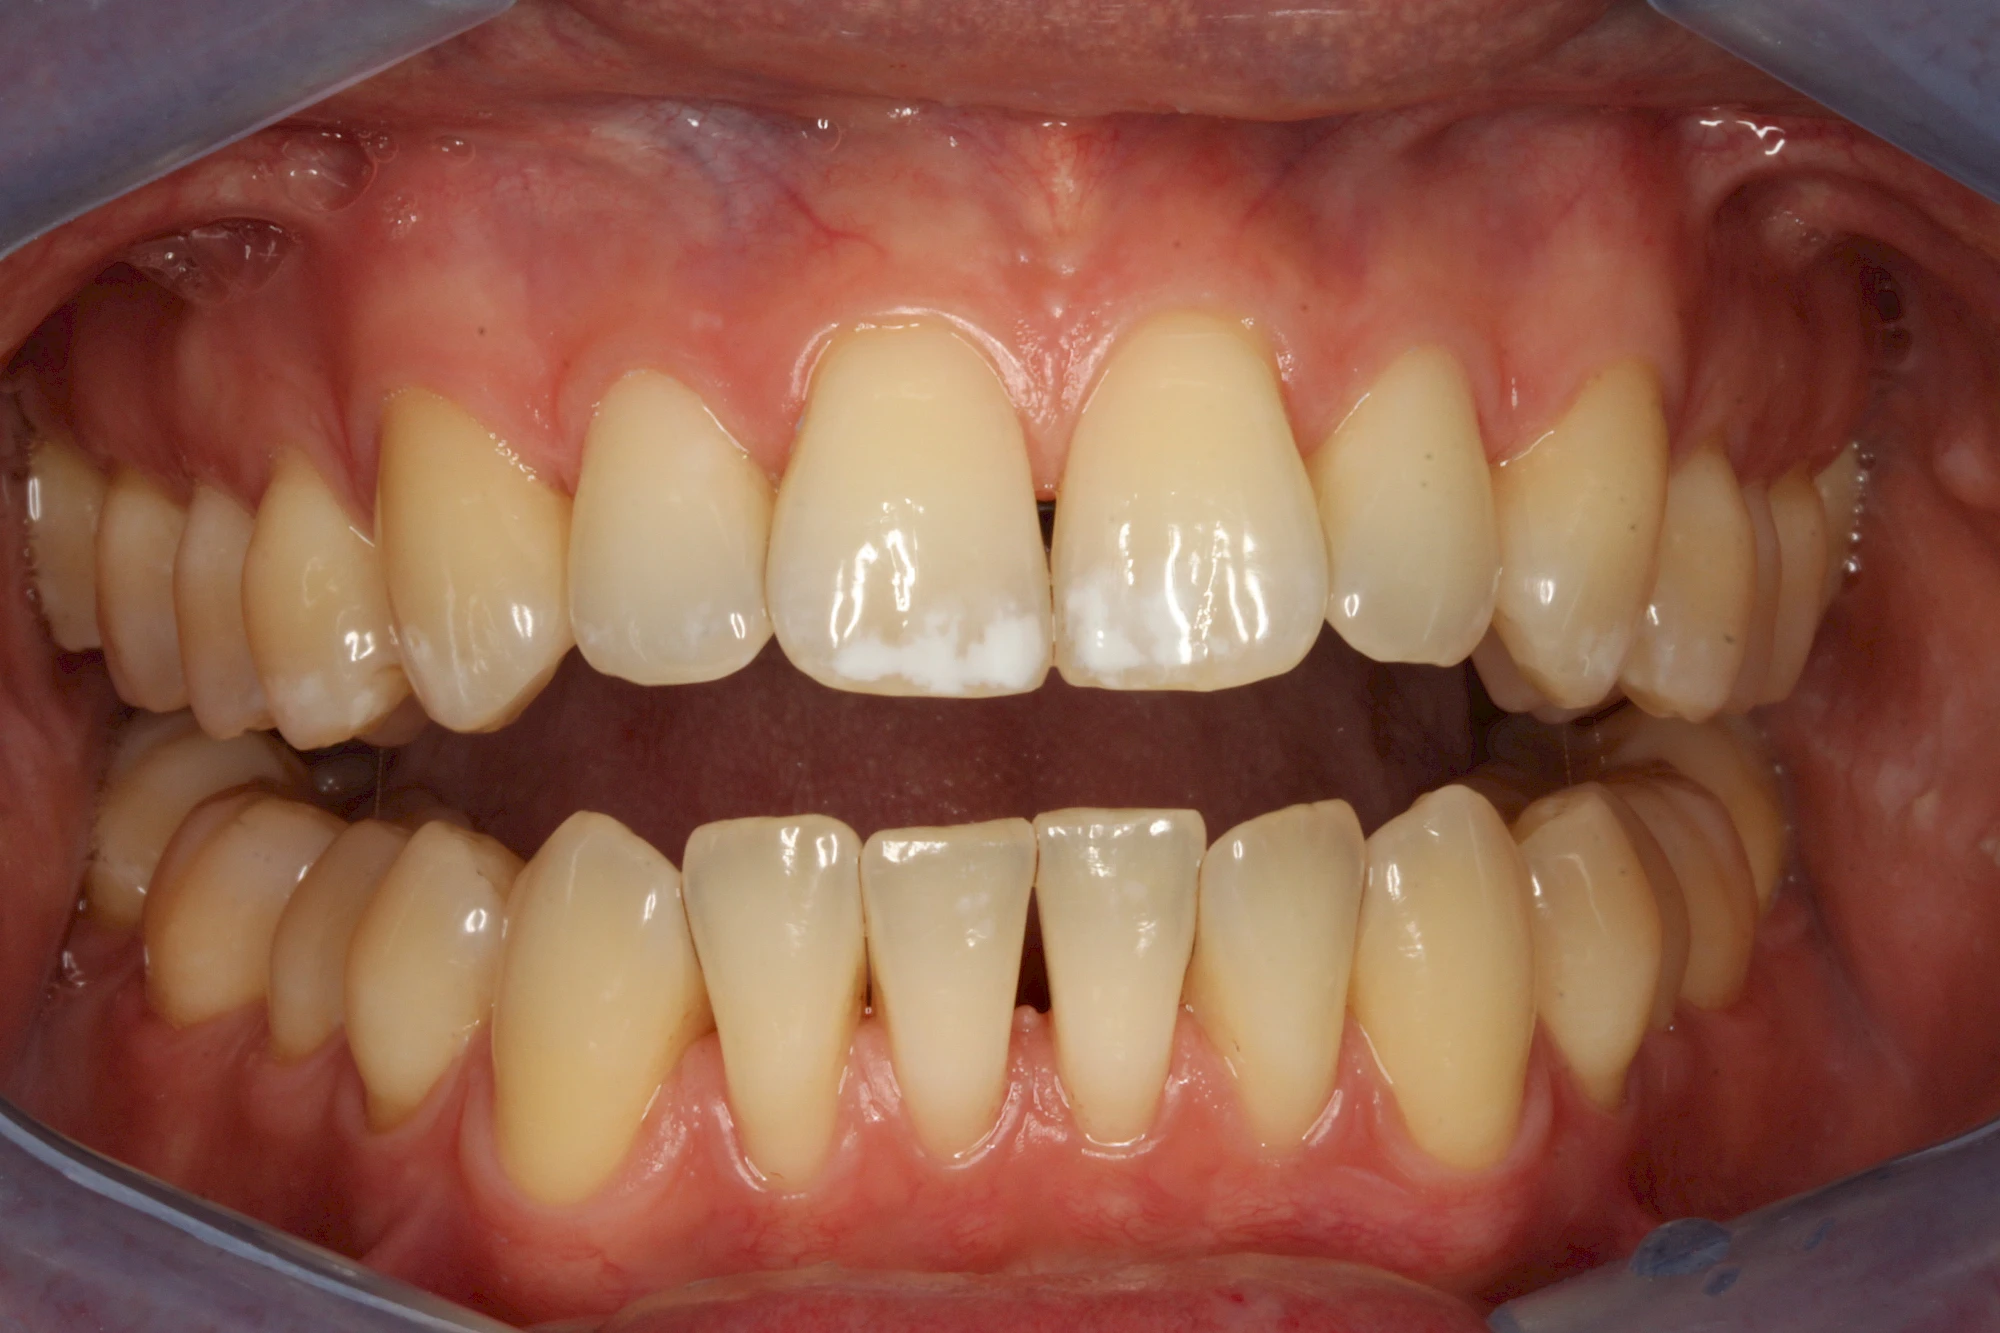

- Durch übermäßige Fluorideinlagerung in der Zahnreifung (mehrere Zähne, weißlich-fleckig)

Gerade bei Kindern und Jugendlichen werden zunehmend häufiger bräunliche Verfärbungen mitunter auch mit Formveränderungen (die Oberfläche ist rauh oder zerklüftet) der Zähne beobachtet. Meist sind Schneidezähne oder Backenzähne betroffen. Dies könnte ein Hinweis auf sogenannte Kreidezähne (MIH: Molaren-Inzisiven-Hypomineralisation) sein.